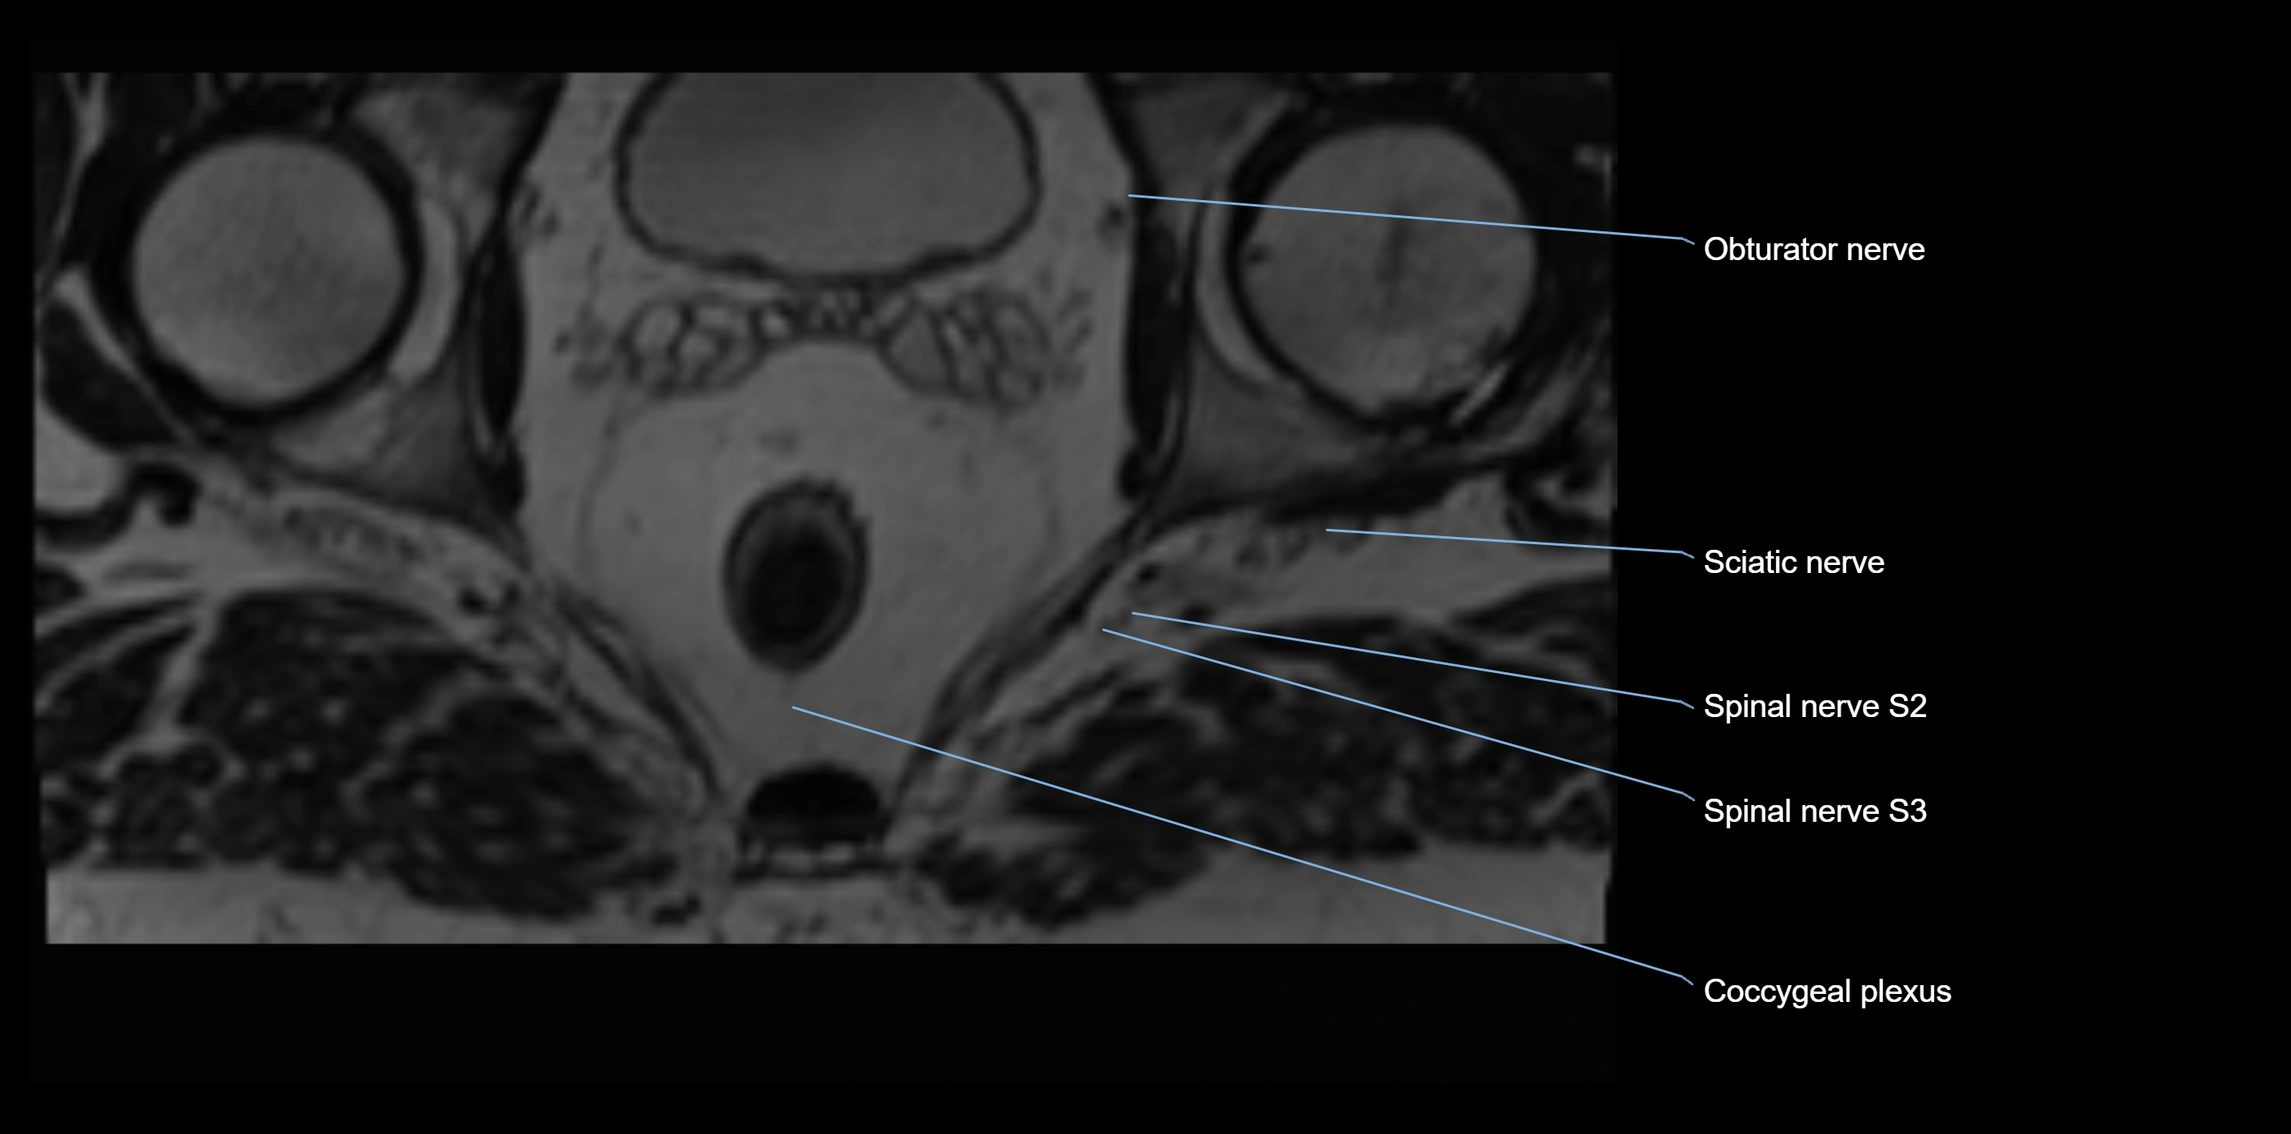

Anococcygeal nerve

The anococcygeal nerve is a small sensory nerve derived from the coccygeal plexus, which itself is formed by the ventral rami of S4, S5, and the coccygeal nerve (Co1). Although tiny, this nerve plays an important role in supplying the skin of the coccyx and the area between the anus and coccyx. It passes through the sacrotuberous ligament and runs in the midline behind the coccyx.

Despite its small size, the anococcygeal nerve is clinically important because of its involvement in coccygodynia (coccyx pain) and perineal pain syndromes.

Origin, Course, and Branches

• Origin:

• Arises from the coccygeal plexus, formed by ventral rami of S4, S5, and Co1

• Course:

• Emerges through the sacrotuberous ligament near the coccyx

• Runs in the midline posterior to the coccyx

• Passes forward into the small space between anus and coccyx

• Branches:

• Small cutaneous branches that supply the skin between the coccyx and anus

MRI Appearance

T1-weighted images:

• Nerve appears as a very thin low-to-intermediate signal intensity structure

• Surrounded by bright fat, aiding visualization

T2-weighted images:

• Nerve shows intermediate to mildly hyperintense signal compared to muscle

• Pathological involvement appears brighter

STIR (Short Tau Inversion Recovery):

• Normal nerve appears dark

• Inflamed or entrapped nerve appears bright hyperintense

T1 Fat-Sat Post-Contrast:

• Normal nerve enhances minimally

• Pathologic nerve (neuritis, entrapment, tumor infiltration) shows focal or diffuse enhancement

3D T2 SPACE / CISS:

• Nerve appears intermediate to mildly hyperintense compared to muscle

• Surrounded by bright fat or CSF, improving visualization

• Best sequence for mapping small pelvic nerves such as the anococcygeal

MRI image

image